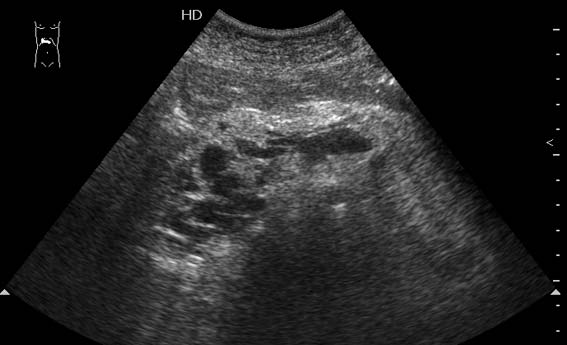

Тромбоз верхней брыжеечной вены

Женщина средних лет, клинический диагноз при поступлении - хронический панкреатит

данные изменения могут соответствовать и хроническому панкреатиту и стеатозу поджелудочной железы.

Да, действительно, формирование варикоза в области головки панкреас характерно для тромбоза верхней брыжеечной вены.Брехт писал(а):Верхней брыжеечной

Ургентность здесь относительная, это неострый тромбоз - для развития коллатералей необходимо время. В хирургической клинике при хроническом панкреатите мы нередко видим тромбозы воротной вены, селезеностой вены. Но тромбоз ВБВ встречается нечасто и заподозрить его можно по "гроздьям" варикозов в области головки панкреас. На пилетромбоз обычно указвают "гроздья" варикозов в воротах печени.besliu писал(а):Спасибо за случай,впервые вижу такую патологию,ургентность в поликлинике не так уж частая![]()